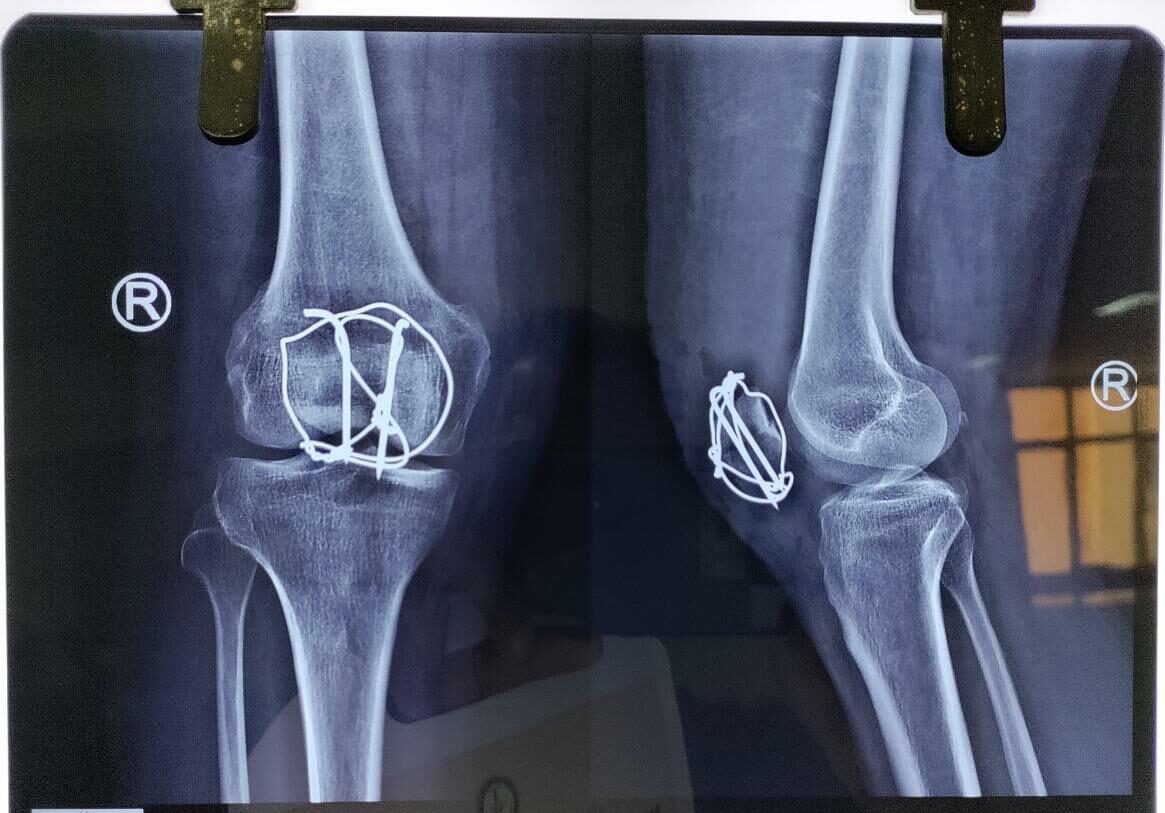

Moments That Mark Meaningful Recovery

Witness real patient transformations at The Ortho Clinic through images that reflect successful treatments and restored mobility.